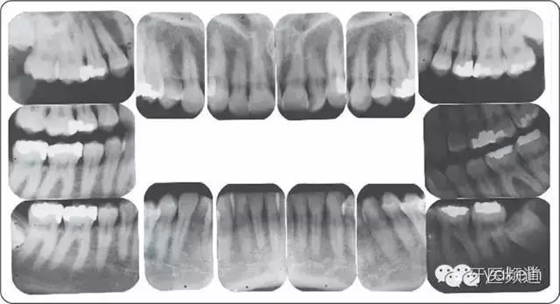

全口根尖片顯示(圖5~圖7):

● 沒(méi)有鄰面骨喪失。

● 充填體邊緣缺損。

● #19根分叉約20%骨喪失,與其他牙齒根分叉區(qū)比較,骨質(zhì)密度減低(透射影)。

● #19近遠(yuǎn)中根尖周透射影。

● 第三磨牙阻生。

● 無(wú)齲齒。

圖5 全口牙齒根尖片。